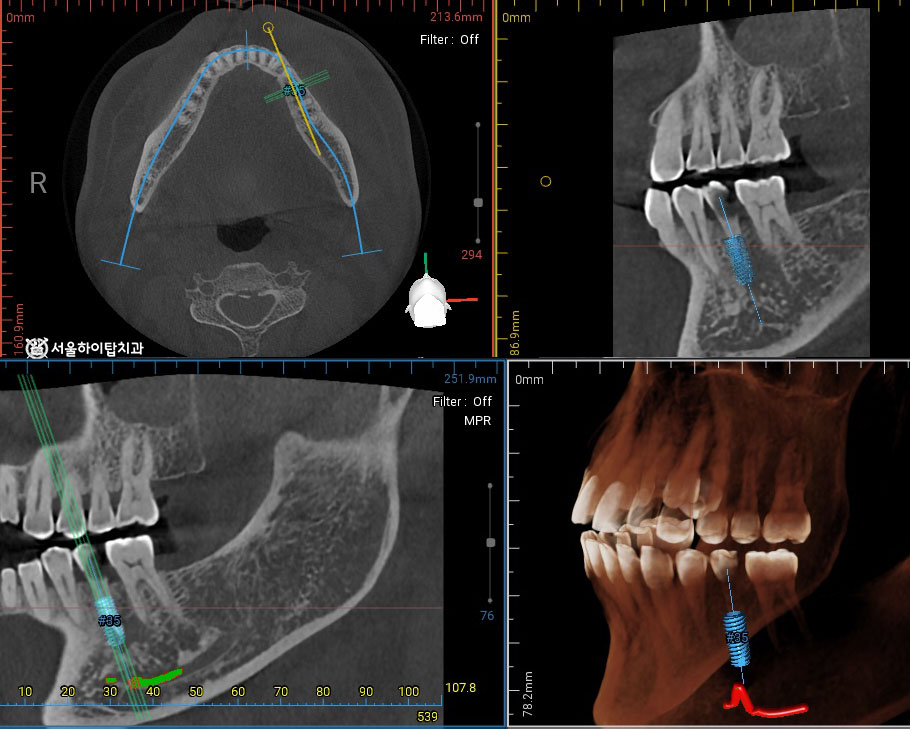

임플란트 가상 식립 시뮬레이션 진행

간석오거리역 치과 에서는

치수 감염이 확인된 상황으로,

잔존 치질의 양과 파절 범위를 고려했을 때

보존적 치료만으로는 장기적인 예후를

기대하기 어려운 상태로 판단되어

발치 후 임플란트를 계획할 수 있습니다.

이 과정에서 CBCT 데이터를 기반으로 한 가상 시뮬레이션을 통해

식립 각도와 깊이, 보철적 중심 위치를 사전에 설계할 수 있습니다.

현재 하치조신경과의 거리는 괜찮습니다.

또한 잔존골의 양과 bone level 도 일정 수준 이상 나와주기 때문에

추가적인 골 이식 없이 임플란트를 식립할 수 있는 소견입니다.